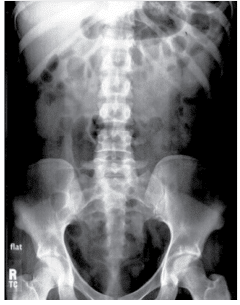

- Radiografia Simples (Plano Simple/Scout): Essencial para avaliar preparo e identificar cálculos radiopacos (90% dos casos). É a base de comparação.

- Fase Nefrográfica (Imediata - ~15-30s pós-injeção): Mostra a opacificação do parênquima renal. Avalia tamanho, contorno e simetria funcional.

A interpretação deve ser sistemática, comparando cada fase com a anatomia normal e com a radiografia simples inicial.

- Contornos Renais: Lisos, com tamanho de 3-4 vértebras.

- Nefrograma: Simétrico e homogêneo.

- Pielograma: Cálices côncavos e afilados. Ureteres finos com peristalse visível.

- Cistograma: Bexiga com contornos regulares.

- Pós-miccional: Esvaziamento quase completo.